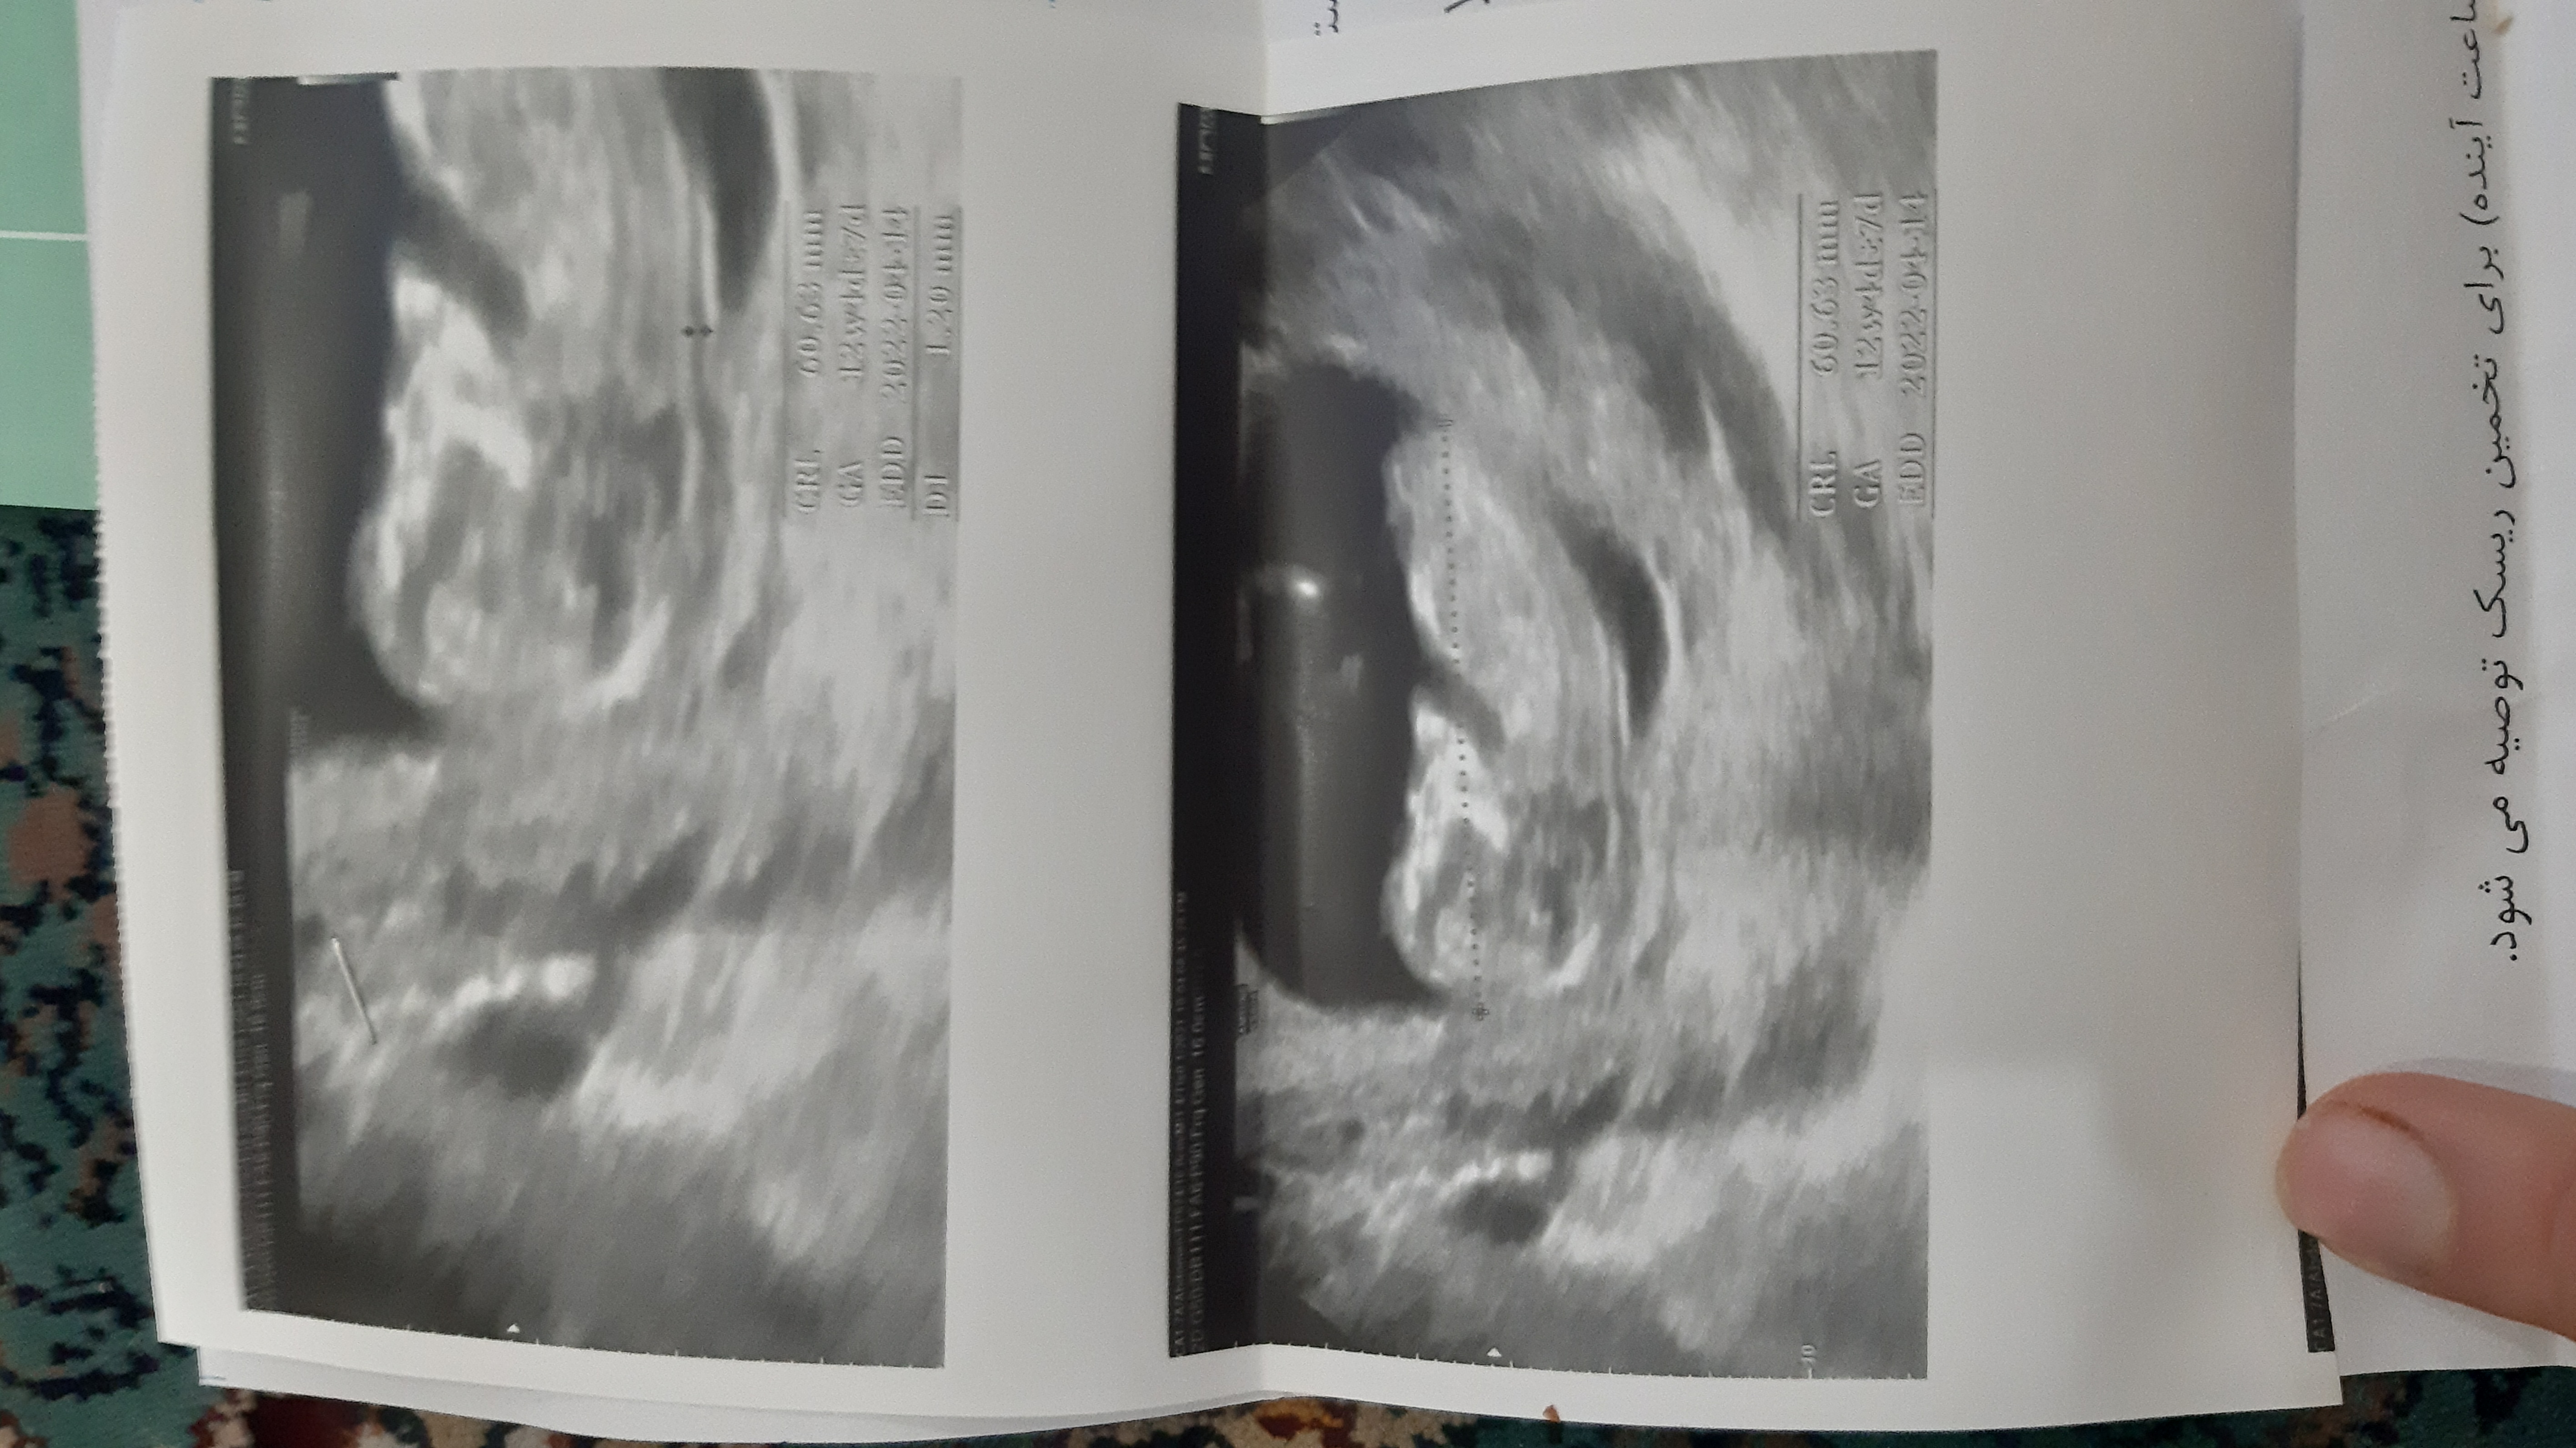

محمدآرادs عضویت: 1400/06/17 تعداد پست: 1224 عزیز من از روی آلت تناسلی میگم.این عکس فقط قسمت جمجمه س سلام میشه برای منم بگین لطفا

محمدآرادs عضویت: 1400/06/17 تعداد پست: 1224 احتمال زیاد دختر عکس سونو من دقیقا شبیه سونو شمایه از روی چی گفتین

123sanazjoon عضویت: 1400/09/13 تعداد پست: 200 احتمال زیاد دختر سلام عزیزم خیلی ممنون میشم از منم حدس بزنی